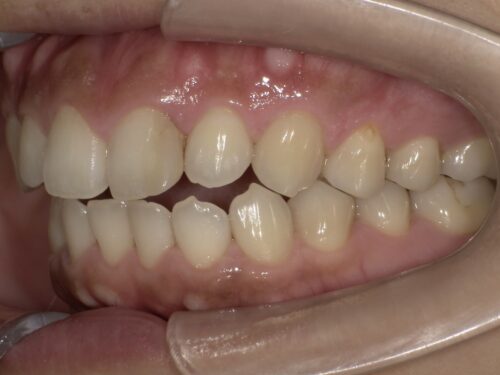

真正面だけでなく、

横から見たり、

噛む面から見たりと、この詰め物の状態をよく確認します。

また、

レントゲンでも詰め物の奥で再びむし歯になっていないか等、

色以外にほかに問題点がないか検査が必要です。

今回はとくに問題ありませんでした。